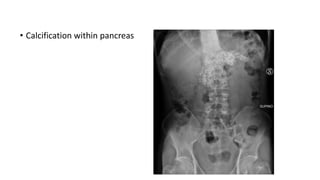

Investigation Findings

AXR • Sentinel loop –localized ileus of small intestine

• Gallstone, pancreatic calcification

• Calcification within pancreas

• Investigations

-pancreatic calcification on AXR